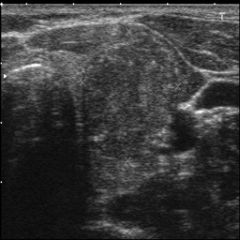

Thyroid nodule segmentation in the ultrasound image is critical for accurate thyroid disease diagnosis Tessler et al. (2017); Chen et al. (2020), but suffers from the blurred structures of anatomy with speckle noise, making it highly dependent on the expertise of the radiologist Khor et al. (2022). Employing deep learning algorithms Chen et al. (2022); Chi et al. (2023); Ozcan et al. (2024); Xiang et al. (2025) for thyroid nodule segmentation can significantly enhance diagnostic efficiency for healthcare professionals. While fully supervised algorithms Ronneberger et al. (2015); Cai et al. (2020); Zheng et al. (2021); Cao et al. (2023); Tao et al. (2022) achieve promising performance on specific datasets where precise ground truth masks are available for training, acquiring a large number of delicate annotations remains resource-intensive and time-consuming Liu et al. (2024).

For thyroid nodule segmentation, weak supervision has been considered as a trend with various promising models have been proposed. However, due to the quality of ultrasound images and the morphological variability of nodules, applying weak supervision to thyroid nodule segmentation in ultrasound images still faced two issues: pseudo-label noise and irrational learning strategies.

As shown in Fig. 1, we propose a novel weakly supervised segmentation (WSS) framework named HCHR for thyroid nodule segmentation. The framework consists of a high-confidence multi-level labels generation flow and a high-rationality multi-level learning strategy branch. In the label generation flow, we integrate prompted MedSAM results with geometric transformations of point annotations to generate high-confidence labels as training references. In the learning strategy branch, we compare multi-level attributes between predictions and generated labels by combining alignment loss, contrastive loss, and prototype correlation loss, in order to jointly learn segmentation location and delicate shape information with high rationality.